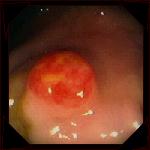

Опухоль в кишечнике

Карциноиды - небольшие (размером с вишню) разрастания, возникающие преимущественно в органах пищеварительного тракта: желудке, двенадцатиперстной, тонкой и толстой кишке, поджелудочной железе; иногда в слизистой оболочке бронхов или трахеи. Крайне редко карциноидные опухоли локализуются в яичках или яичниках. Опухоли образуются при нарушении развития эмбриона. Карциноиды, в отличие от других злокачественных опухолей, характеризуются очень медленным ростом и поздним метастазированием. Как правило, карциноиды метастазируют в печень.